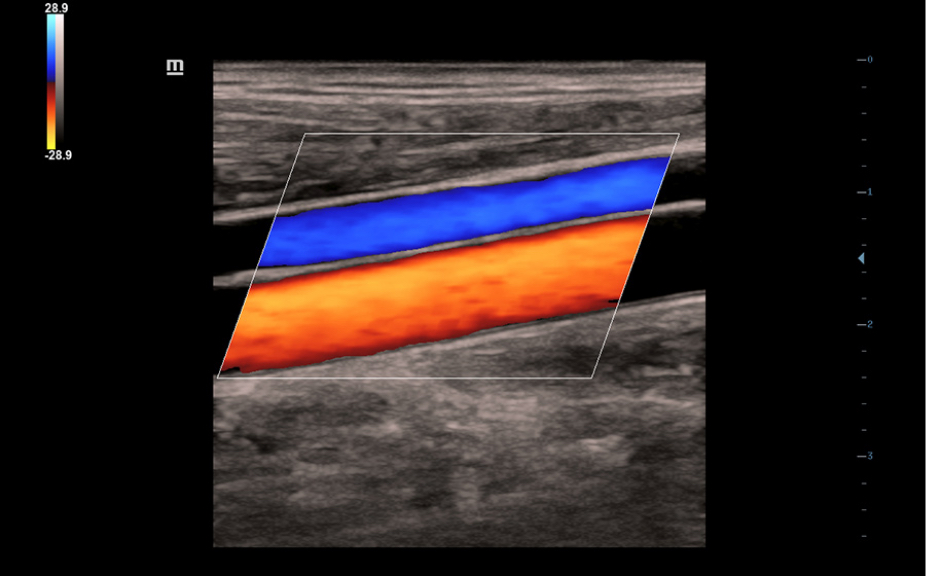

Включает различные режимы визуализации.

Включает различные режимы визуализации.